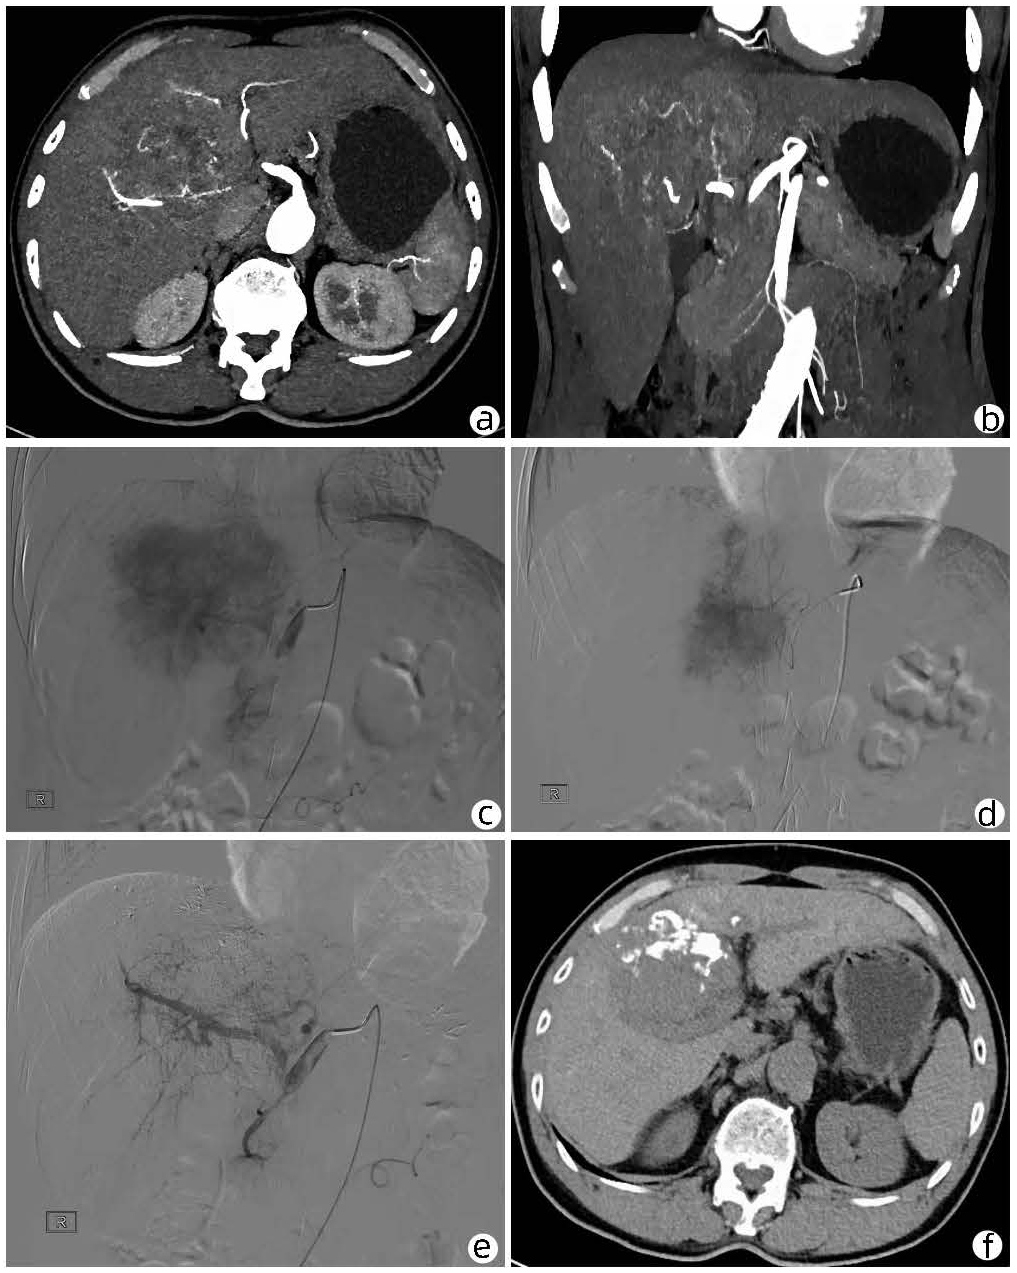

Local embolization combined with targeted comprehensive immunotherapy in treatment of sarcomatoid hepatocellular carcinoma: A case report

Jin LEI, Linzhi ZHANG, Yinying LU, Bowen CHEN, Shi ZUO

2022, 38(4): 880-882. DOI: 10.3969/j.issn.1001-5256.2022.04.026

Abstract(1335) HTML (456) PDF (3487KB)(84)

Abstract: